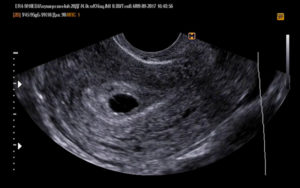

Показатели УЗИ

• Сердцебиение эмбриона не определяется. В норме на ультразвуковом исследовании оно заметно, начиная с 5 недели беременности.

• Плодное яйцо не имеет диаметра таких размеров, которые предполагает срок беременности.

• Величина эмбриона, находящегося в плодном яйце, не соответствует сроку беременности.

• Если срок до 4 недель, то признаком гибели плодного яйца является деформация.

• Эмбрион не визуализируется на сроке 6 – 7 недель.